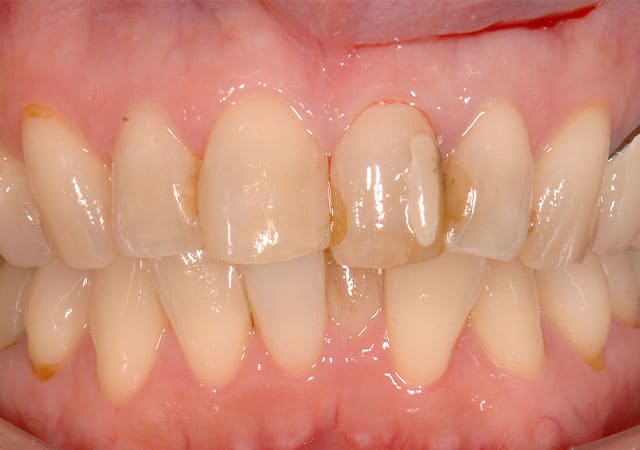

左上の前歯の見た目が気になることを主訴に来院されました。

虫歯を除去後、神経が露出しないように丁寧に削合しました。

仮歯に置き換え、見た目の確認をしてもらいました。

反対側に近い形となっており、元々の歯よりも大きいため、全体的に小さくしてほしいとの希望でした。